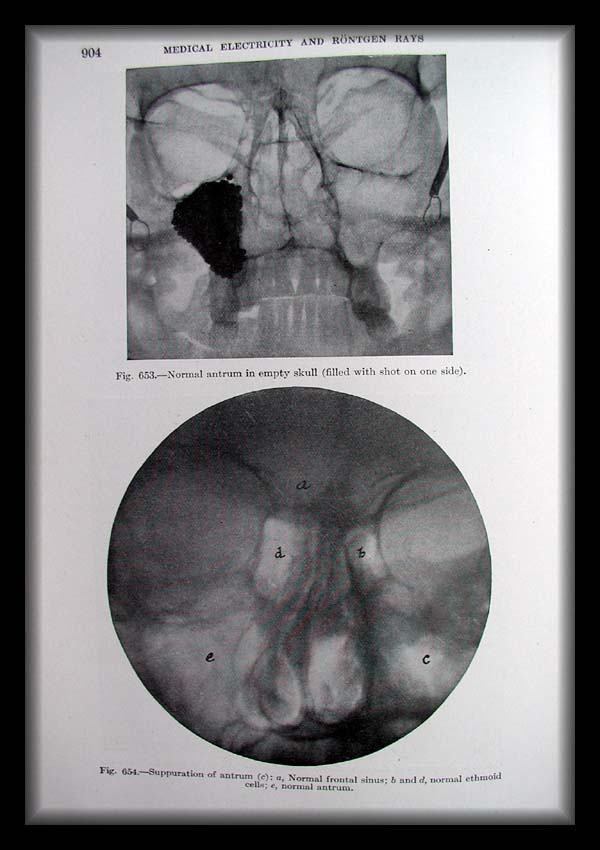

Page0904